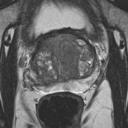

We present a novel technique to discover and exploit weak causal signals directly from images via neural networks for classification purposes. This way, we model how the presence of a feature in one part of the image affects the appearance of another feature in a different part of the image. Our method consists of a convolutional neural network backbone and a causality-factors extractor module, which computes weights to enhance each feature map according to its causal influence in the scene. We developed different architecture variants and empirically evaluated all of our models on two public datasets of prostate MRI images and breast histopathology slides for cancer diagnosis. To confirm our quantitative results, we conduct ablation studies and investigate the explainability of our models via class activation maps. Our findings show that our lightweight block extracts meaningful information and improves the overall classification, together with producing more robust predictions that focus on relevant parts of the image. That is crucial in medical imaging, where accurate and reliable classifications are essential for effective diagnosis and treatment planning.